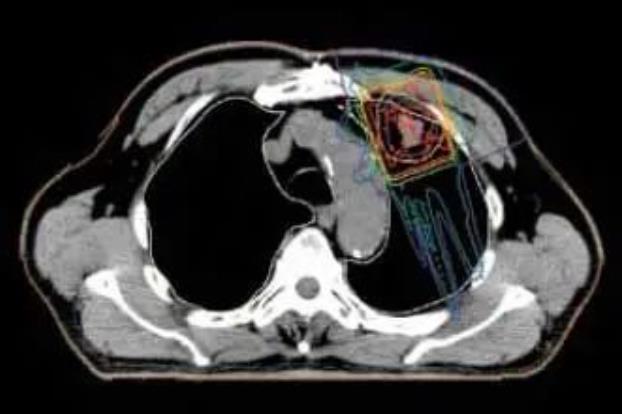

肺癌根据癌细胞的形态可以分多种类型。对于病灶局限于肺部的肺癌,根据病灶的位置,最短的治疗时间约为2周(门诊治疗)。对于有附近淋巴结转移的晚期非小细胞肺癌,通常需要联合化疗进行6~7周的质子治疗。每次治疗大约20分钟,对病灶的照射时间只有2~3分钟。

与传统的放射治疗相比,质子治疗减少了对肺部和心脏、骨髓等器官的辐射量,并降低了治疗的副作用。

质子治疗可以减少对周围正常肺组织的照射剂量,只对病变部位进行集中照射。